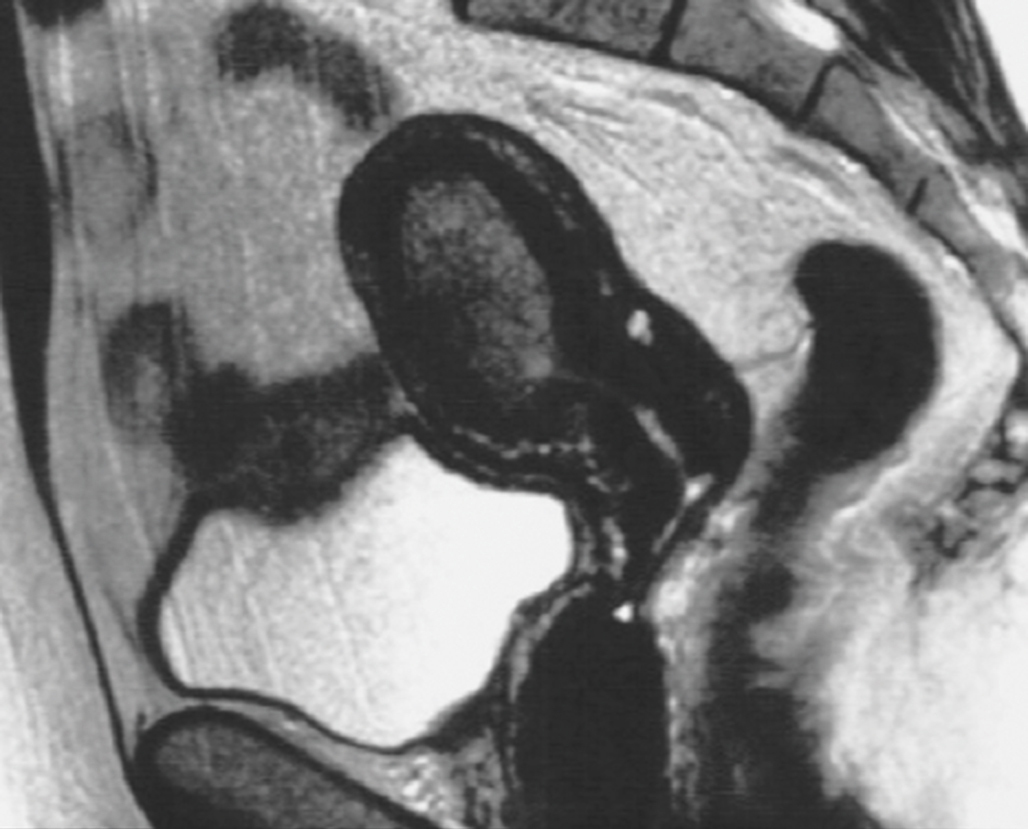

Quel est votre diagnostic ?

Il s'agit d'une IRM pelvienne révélant un cancer de l'endomètre. Le cancer de l'endomètre est le cancer gynécologique pelvien le plus fréquent en France. Il est suspecté devant des métrorragies post-ménopausiques qui doivent faire l'objet d'un bilan étiologique. Le pronostic favorable des stades localisés (survie relative à 5 ans = 95 %) renforce la nécessité d'un diagnostic précoce. Contrairement au cancer du col de l'utérus, il n'existe pas de dépistage du cancer de l'endomètre. L'IRM pelvienne associée à une exploration des aires ganglionnaires lombo-aortiques est l'examen de référence. Cette IRM doit évaluer 5 paramètres : le volume tumoral, le degré d'infiltration myométriale, la présence d'adénopathies iliaques ou lomboaortiques, l'atteinte éventuelle du col ou des organes de voisinage.